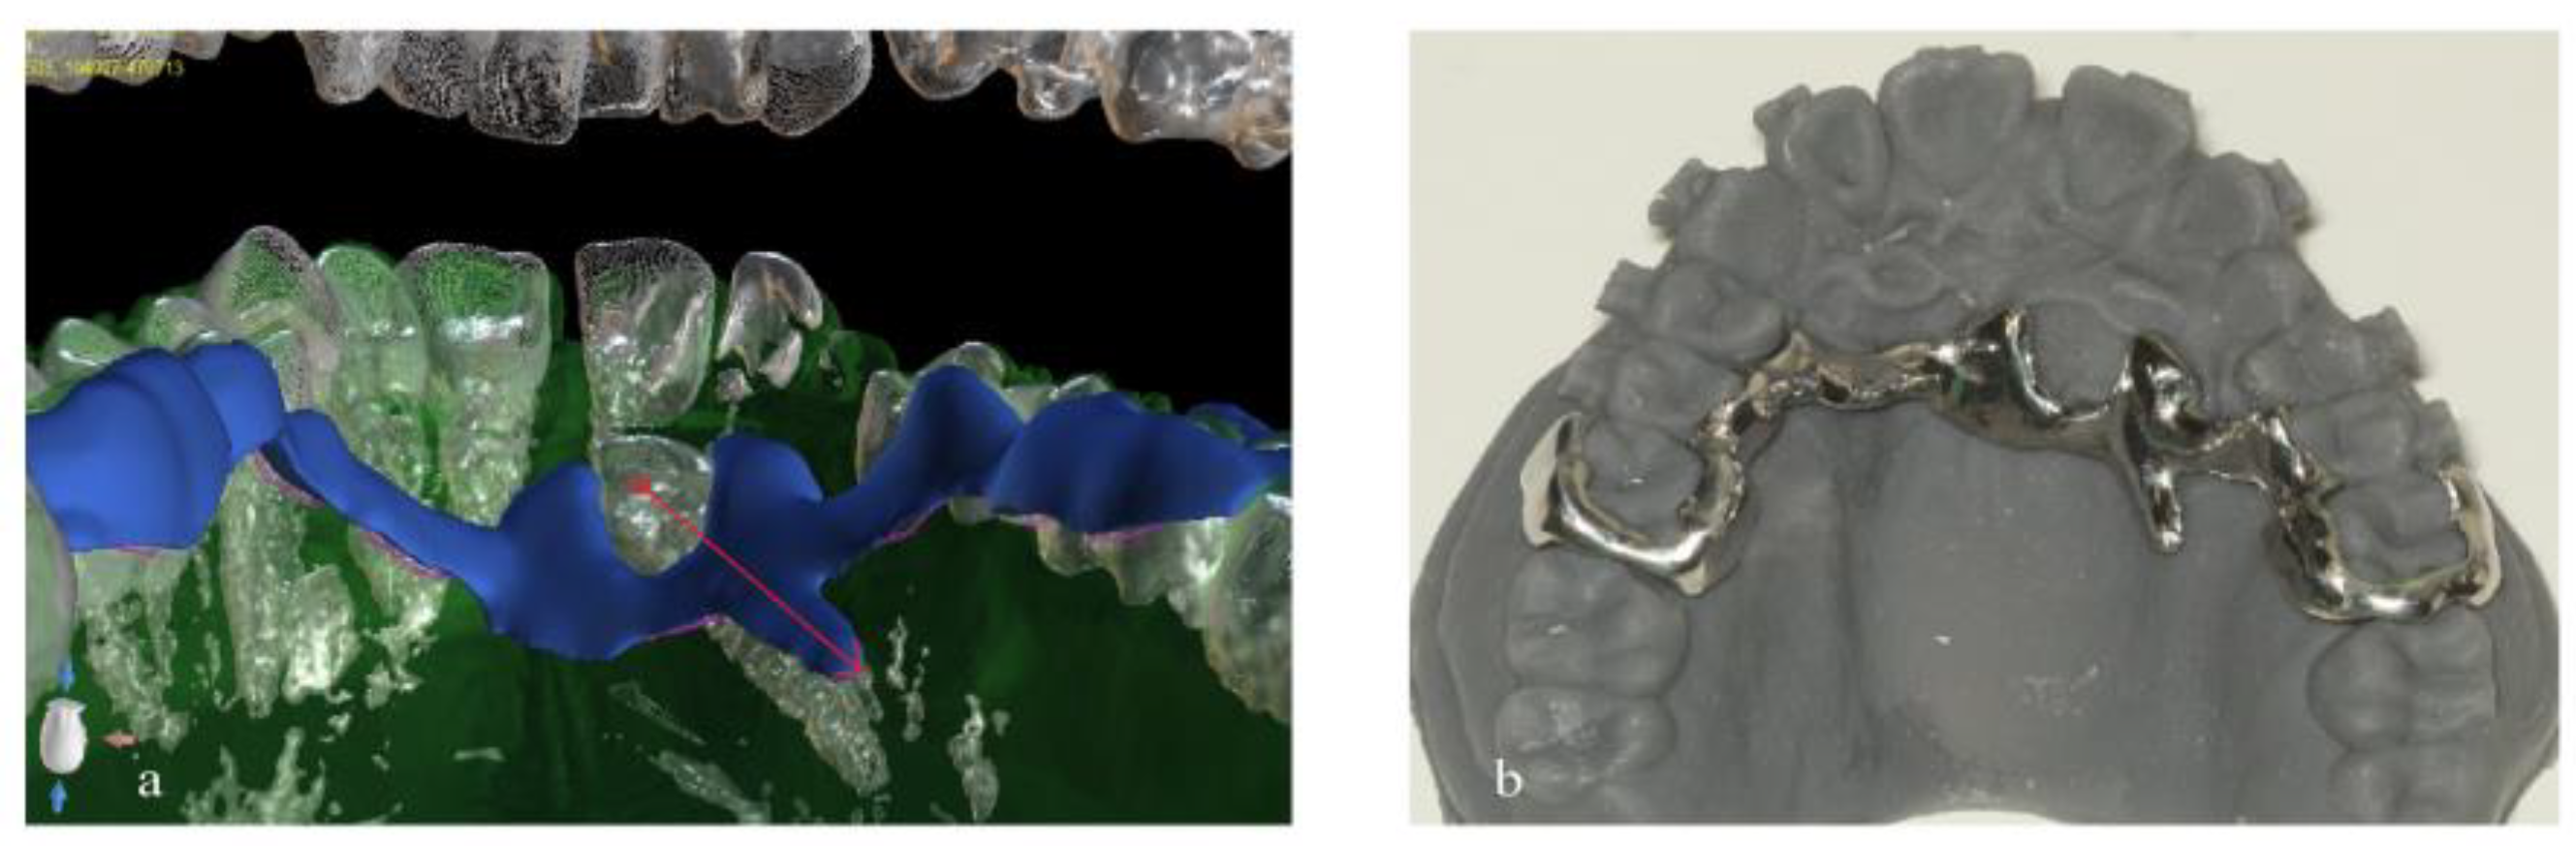

2. Materials and Methods

3. Results